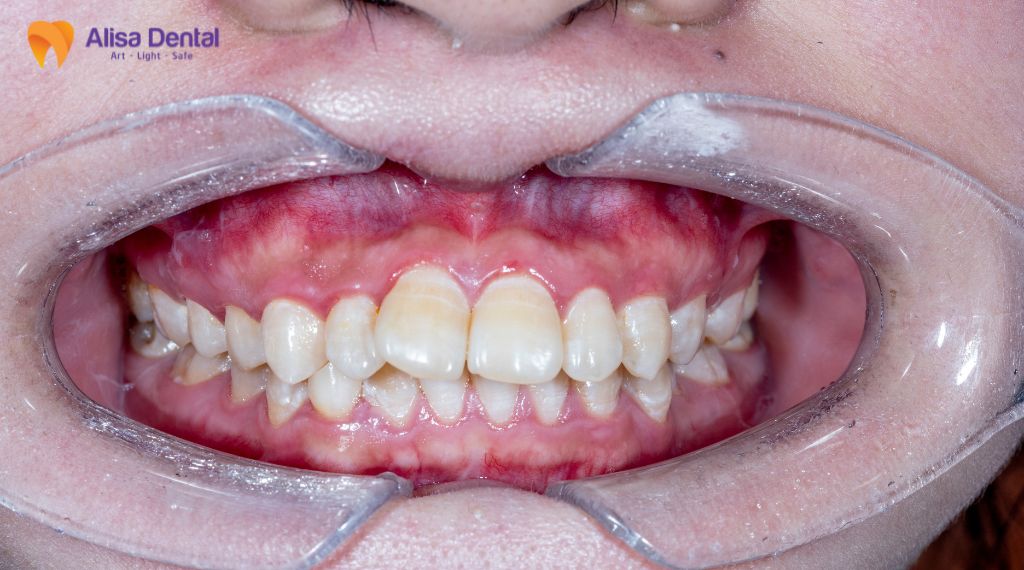

Trường hợp 4: Răng làm phục hình thẩm mỹ (bọc sứ)

Không phải trường hợp bọc răng sứ nào cũng cần lấy tủy. Tuy nhiên, đây là chỉ định bắt buộc trong các tình huống răng mọc lệch lạc nhiều, hô, móm hoặc chen chúc mà khách hàng muốn bọc sứ để dàn đều cung hàm (thay vì niềng răng).

Để đưa các răng này về đúng vị trí thẳng hàng, bác sĩ buộc phải mài đi một lớp mô răng khá dày, đôi khi xâm lấn vào khoảng sinh học hoặc sát buồng tủy. Nếu không chữa tủy dự phòng (chủ động lấy tủy trước), sau khi gắn răng sứ, bệnh nhân sẽ gặp phải tình trạng ê buốt kéo dài, đau nhức hoặc viêm tủy sau 1 thời gian ngắn sử dụng, dẫn đến việc phải tháo sứ ra làm lại rất tốn kém và phiền toái.